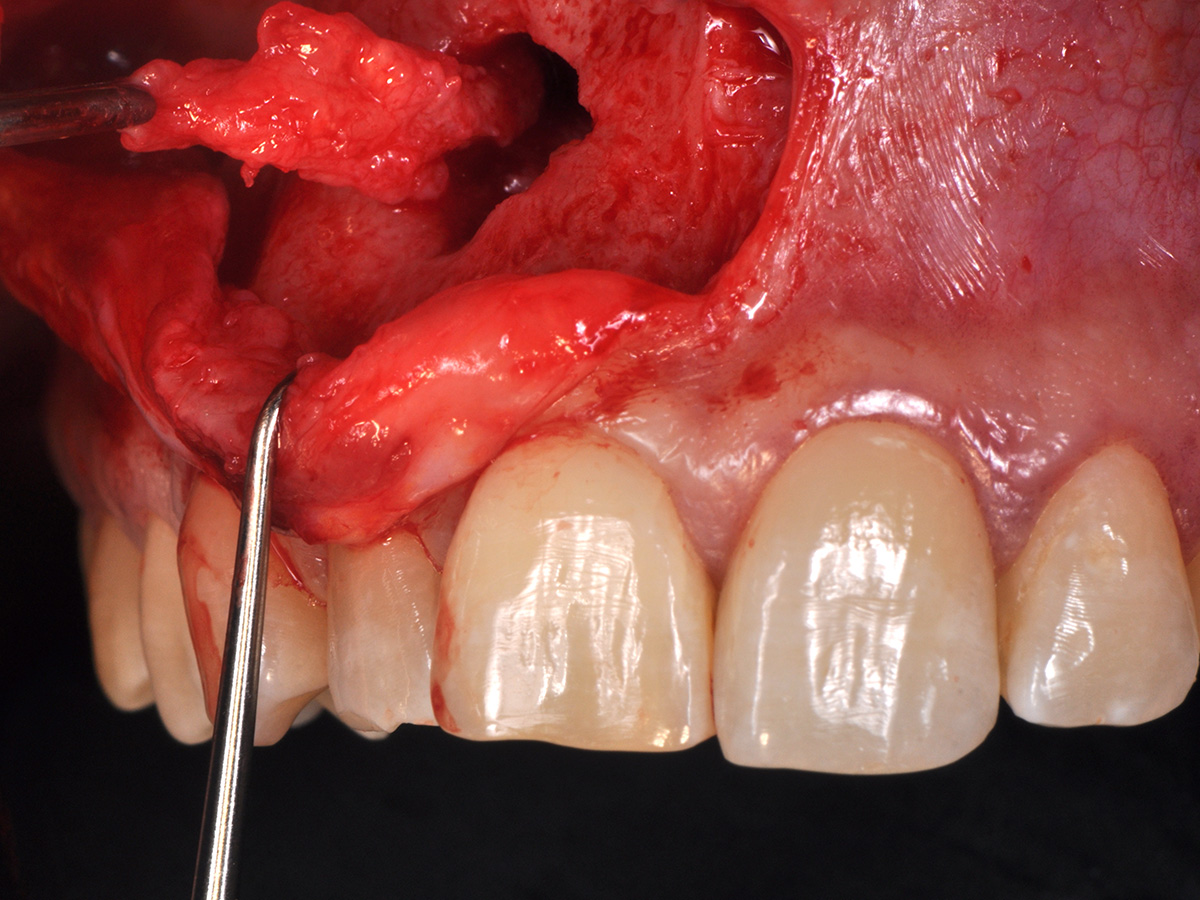

Abbildung 10

Nach vestibulärer Freilegung wurde die Zyste vollständig entfernt und zur histopathologischen Untersuchung eingesandt.

Mit der Patientin wurde der Versuch des Zahnerhaltes trotz ausgedehnter Zyste besprochen. Gleichzeitig sollte das Zystenlumen zu einer sicheren ossären Durchbauung geführt werden, um eine implantologische Sofortversorgung vorzubereiten, falls zu einem späteren Zeitpunkt eine Zahnentfernung notwendig werden sollte. In der Phase vor der geplanten Operation wurden die Wurzelkanalfüllungen an Zahn 11 und 12 durch einen Endodontologen alio loco revidiert. Die Schnittführung wurde aufgrund des bestehenden „Gummy Smile“ hoch im Vestibulum geführt – so konnte die delikate Parodontalstruktur in ihrer Form unangetastet belassen werden, um einen möglichst optimalen ästhetischen Erfolg zu erreichen (Abb. 8, 9). Nach vestibulärer Freilegung wurde die Zyste vollständig entfernt und zur histopathologischen Untersuchung eingesandt (Abb. 10). Anschließend erfolgte eine Wurzelspitzenresektion an den Zähnen 11 und 12 durch die vestibuläre ossäre Perforation (Abb. 11), gefolgt von einer ultraschallbasierten, retrograden Kanalaufbereitung und Abdichtung mit MTA. Um die knöcherne Durchbauung am Boden der Zyste osteoinduktiv zu unterstützen, wurden mit Hilfe eines mechanischen Knochenschabers aus dem Bereich des rechten naso-palatinalen Pfeilers Knochenchips entnommen und als erste basale Augmentationsschicht in den ossären Defekt eingebracht (Abb. 12). Der größere Anteil von 80 % des Defektvolumens wurde mit einem vollständig resorbierbaren, xenogenen Augmentationsmaterial aufgefüllt (Abb. 13) (mp3®, OsteoBiol®). Der Defekt wurde zum Vestibulum hin mit einer stabilen, vollständig degradierbaren Membran abgedeckt (Abb. 14) (Soft Cortical Lamina, OsteoBiol®). Zum einen wurde hiermit im Sinne der GBR das Weichgewebe vom Augmentat getrennt. Zum anderen verhinderte die stabile Membran das Einwachsen eines Weichgewebeankers in den Defekt und damit eine narbige Verziehung im Vestibulum. Um eine Verschiebung der Membran zu vermeiden, wurde diese mit zwei Titanpins in der Kortikalis fixiert. Die Pins wurden bei Beschwerdefreiheit in situ belassen (Titan-Bone-Pin-System). Der Wundverschluss erfolgte einschichtig mit nicht resorbierbarem Nahtmaterial (Abb. 15) (Seralene® 5-0 DS-15). Peri- und postoperativ wurde eine antibiotische Abschirmung unter Fortführung für insgesamt drei Tage mit Amoxiclav 875/125 1-0-1 durchgeführt.